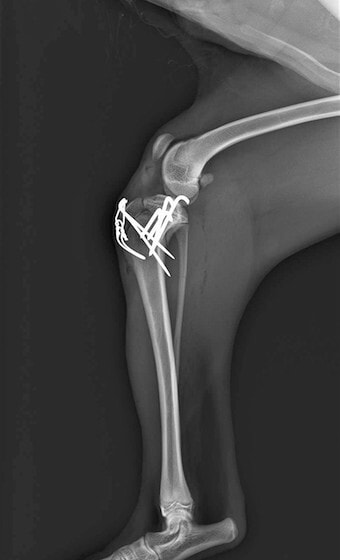

症例3:キルシュナーワイヤーのピンニングによる整復

ペルシャ猫 11ヶ月齢 雄

他院にて左大腿骨遠位の成長板骨折(salter-harrisⅠ型)が認められており、治療相談を目的として来院。当院にて、キルシュナーワイヤーを用いたピンニングにより骨折部位の整復を行いました。術後の経過は良好で、現在も経過観察中です。

術前レントゲン

術後レントゲン

機器

Arthrex社のターゲティングデバイスを用いてピンニングの位置を調整することで、確実な固定を行っています。当院ではこの手術器具以外にも、人の手術にも使用される様々な器具を導入し、手術精度を高め、また医療メーカーと新しい器具の開発、試作にも取り組んでおります。